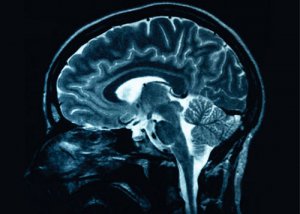

英国一项最新研究显示,对因中风而丧失部分行动能力的患者来说,如果使用微弱电流刺激大脑中的特定部位,可以帮助他们改善行动能力。

据介绍,中风导致患者失去部分行动能力的原因是大脑相关部位中的神经元之间连接不畅。以前曾有研究证实用微弱电流刺激大脑可增强神经元的活动性,本次研究中用电流刺激的是大脑中与行动能力有关的部位,结果证实了用这种方法可以帮助神经元恢复连接,从而起到治疗中风的效果。